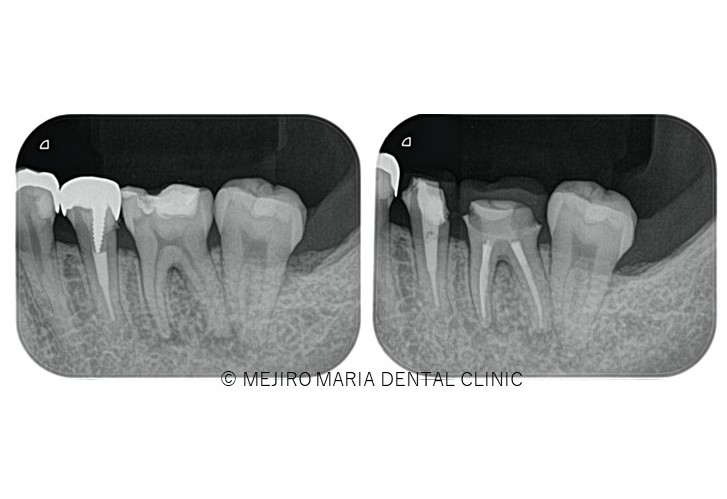

治療終了後、良好に根の中にバイオセラミックが充填され封鎖できていることを確認し(画像A)、3ヶ月後の経過観察にて、痛みや違和感がないことはもちろんのこと、術前、術後に確認できていた根尖性歯周炎の透過像の縮小を確認(画像B)し経過が良好であると判断しました。

また、個人差はありますが、治療後の病変(根尖性歯周炎)のレントゲン像に変化が見られるのはおおよそ3ヶ月後であることから、当院では根管治療終了3ヶ月後に経過観察を行い外科的歯内療法(歯根端切除術)の必要性を判断しております。